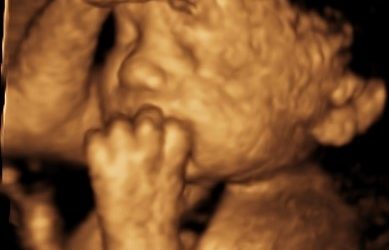

Early Pregnancy & Viability Scans • Gender Scans • Growth & Well-being Scans • 4D Scans

4d and Growth Scans – What to expect at your appointment

Written by Beata Anderson, Advanced Practitioner Sonographer If you are visiting us for a Growth Scan with 4D, you may have one or more of the common questions we are asked. Here we provide the answers, preparing you in advance about what to expect from your booking....